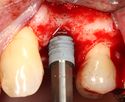

A series of slow-speed drills create and gradually enlarge a site in the jaw for the implant to be placed. The hole is called an osteotomy.

Once the bone is exposed, a series of drills create and gradually enlarge a site (called an osteotomy) for the implant to be placed.

The implant fixture is turned into the osteotomy. Ideally, it is completely covered by bone and has no movement within the bone.